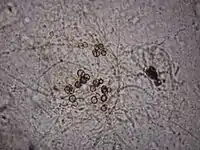

El diagnóstico de la cromomicosis se confirma en el examen directo al demostrar en una lámina con KOH al microscopio la presencia en las escamas y costras de las lesiones, de cuerpos escleróticos pigmentados. Para ello se toma una muestra de las escamas o costras y se coloca sobre una lámina portaobjetos con una gota de KOH al 30 % y se cubre con un cubreobjetos. Al cabo de un reposo de 30 min se observa al microscopio en busca de los cromomicetos descritos (cuerpos de Medlar), solas o agrupadas de color café que pueden estar divididas por un tabique central, dándole el aspecto de grano de café.